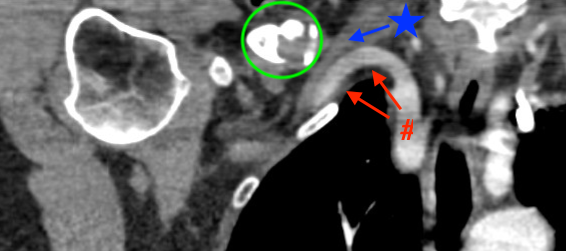

Vascular injury

CT scan: green circle - clavicle nonunion, red arrows - subclavian artery, blue arrow - subclavian vein

Subclavian vein injury

Subclavian vein may be adhered to periosteum medially

- instrumentation medially and inferiorly must be subperiosteal

- careful with medial screws